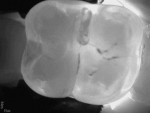

Another promising imaging technology that has come to market over the last few years is the CariVu (Dexis). It uses a wavelength of light that facilitates near-infrared transillumination to detect caries on both the occlusal and proximal surfaces as well as cracks (Figure 5 and Figure 6). At this relatively long wavelength, enamel becomes transparent to photons, whereas porous lesions trap and absorb the photons. This phenomenon causes any lesions to appear dark. This technology is especially helpful at diagnosing approximal caries without the need for ionizing radiation. When teeth are illuminated and imaged from the occlusal surface, approximal caries will clearly show up as dark areas extending from the approximal surface towards the dentin. A clinician can then share this image with the patient to easily and clearly show the progression of disease instead of trying to explain radiolucency on a bitewing radiograph. While this technology does not entirely replace bitewing radiographs, it may minimize the need for radiographs among periodontally stable patients. Recent research suggests that near-infrared transillumination is an effective method for diagnosing lesions involving only the enamel as well as those involving the enamel and dentin.8 This technology has also been helpful in visualizing cracks on teeth. Cracks prevent light transmission and will appear as dark spots, alerting the clinician to potentially significant issues and allowing for more conservative treatment.